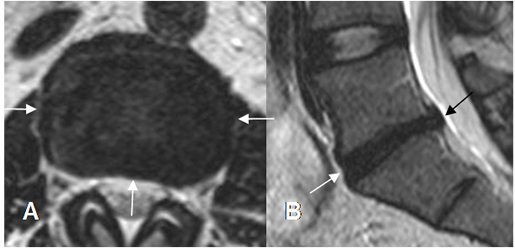

Fig 86. Hernia de disco.

A: TAC axial y B: RM axial en T1. Prominencia asimétrica en contacto con el saco dural, borra la grasa epidural y comprime la raíz, que corresponde a protrusión.